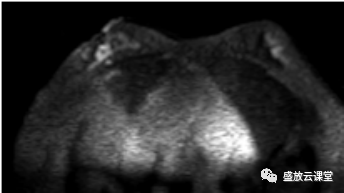

影像学表现

征象分析

特点归纳

诊断结果